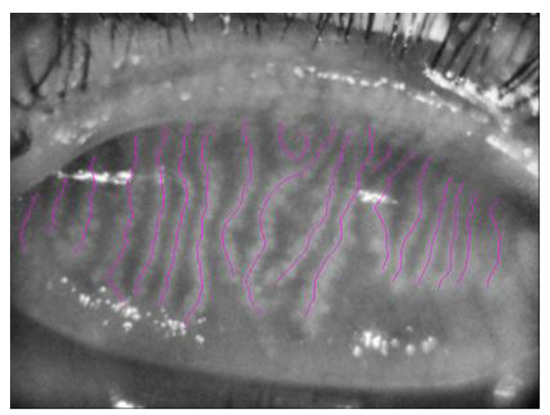

3.2. Meibography Analysis

- Setu, A.K.; Horstmann, J.; Schmidt, S.; Stern, M.E.; Steven, P. Deep learning-based automatic meibomian gland segmentation and morphology assessment in infrared meibography. Sci. Rep. 2021, 11, 7649. [Google Scholar] [CrossRef]